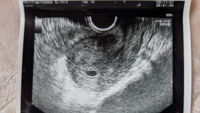

妊娠5週と3日目です 昨日5センチほどの細長い血の塊と言うか 血の皮 Yahoo 知恵袋